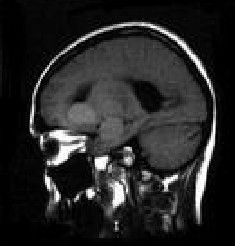

視丘下部損傷X光片視丘下部對人體內的溫度變化自動做出相應的調整.。